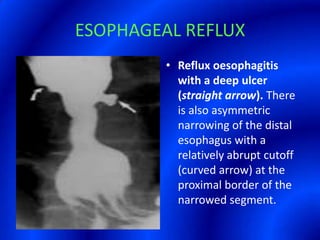

This document provides information about a barium swallow procedure. It begins with an introduction and overview of the embryology and anatomy of the pharynx and esophagus. It then describes the procedure itself, including preparation, technique, views obtained, and indications. Specific conditions that may be examined include pharyngeal and esophageal webs, foreign body impaction, scleroderma, dysphagia, mediastinal masses, and carcinoma. Diagrams are provided to illustrate normal anatomy and various pathological findings.